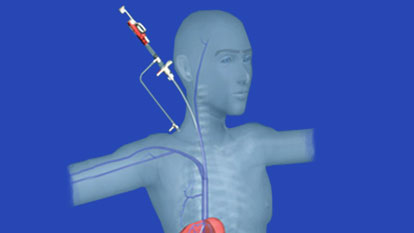

Inferior Vena Cava (IVC) Filter Placement

Inferior Vena Cava (IVC) filter placement is a minimally invasive procedure used to prevent pulmonary...